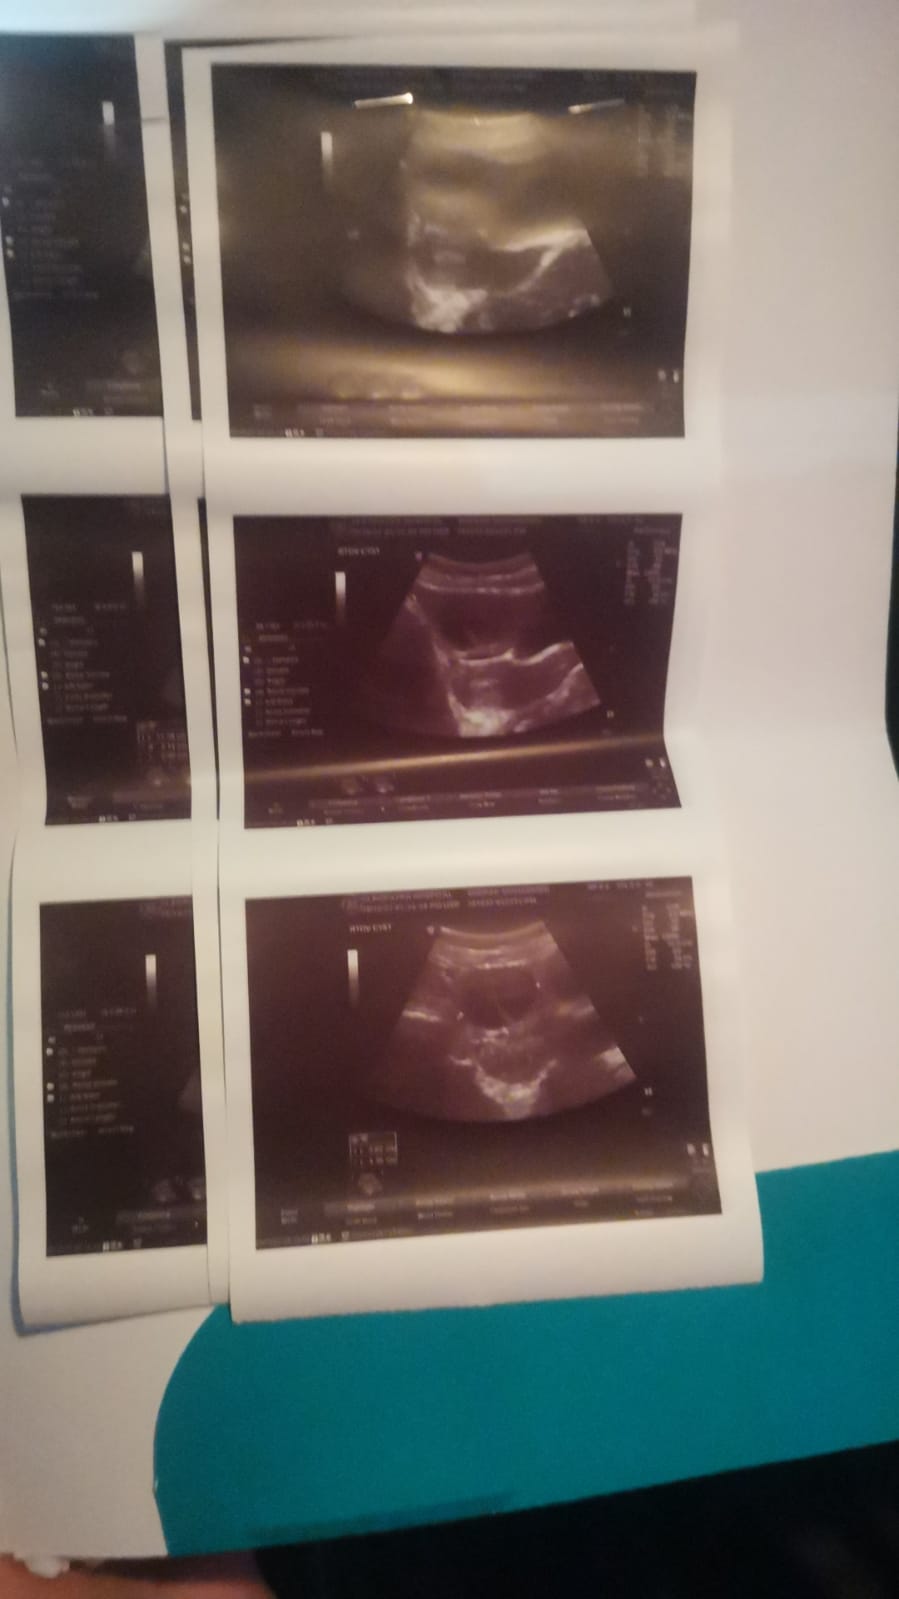

الم شديد في المبيض ناحيه اليمين

انا متزوجة من سنه ولم يحدث حمل وعندي كيس علي المبيض 8في 5 والدكتور عاوز يعملي عمليه جراحيه لازاله الكيس...

عندي كيس ماء علي المبيض الايمن والدكتورة عطتني حقنه ودواء لتنشيط المبيض و ابرة تفجيريه هل يمنع الكيس الحمل ام...

انفجر كيس علي المبيض وهنالك تجلط دم قرب الكيس وحجم الكيس أزد عن أخرى صورة كان حجمه 4.5 والآن 5.5...